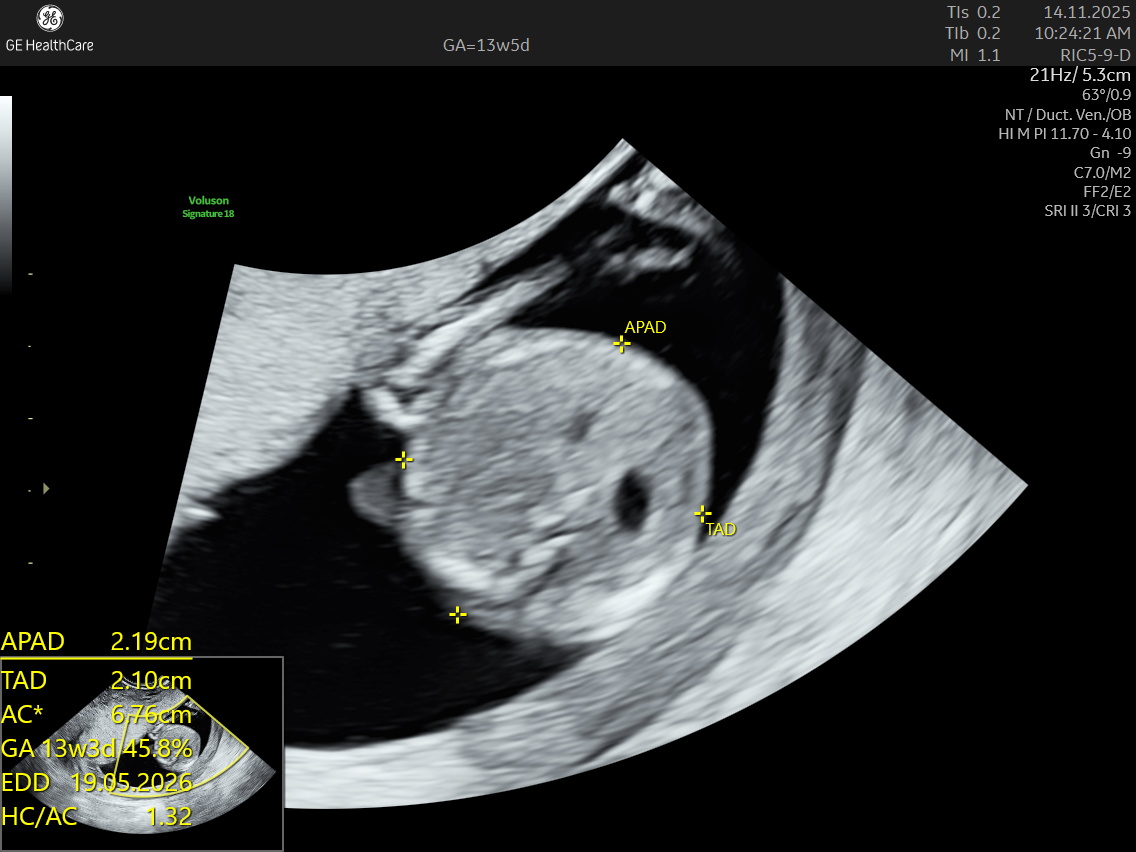

The NT scan is a non-invasive ultrasound examination conducted in the first trimester (12–13 weeks). It measures the nuchal translucency (the fluid at the back of the fetus’s neck) and combines it with the maternal blood test for a detailed risk profile. NT Scan is an important early screening test for Down syndrome (Trisomy 21), Edwards syndrome (Trisomy 18), and Patau syndrome (Trisomy 13).

The NT scan measures the fluid-filled space at the back of the fetal neck, and an increased NT measurement (typically 3.5 mm or more) may indicate a higher risk for:

Although the NT scan is mainly a screening tool and not diagnostic on its own, it can identify about 50% of major fetal abnormalities when combined with other assessments like blood tests and detailed ultrasound. The scan also helps to screen some basic anatomical structures during the first trimester, especially the fetal heart anatomy, brain, face, spine, stomach, abdominal wall, kidneys, bladder, and extremities to varying degrees depending on gestational age and maternal factors.